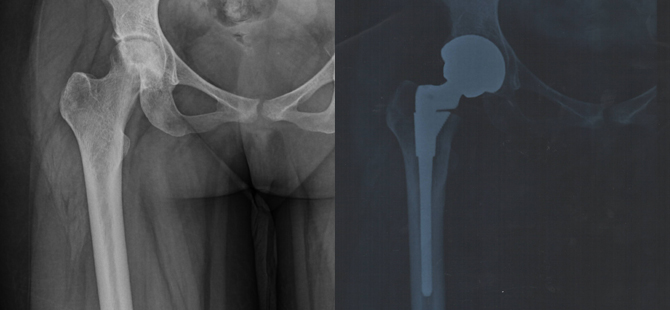

Successful Hip replacement in a patient with sickle cell Anemia

Patient has sickle cell anaemia. The blood cells in this disease are defective and they block the blood vessels. This can cause bone death. This lady had death of the bone in the right hip. She was unable to walk and was in severe pain.

Special Zirconia impregnated delta ceramic on delta ceramic implants which have no friction, produce no debris and can last 80 years were inserted into the patients destroyed hip joint.